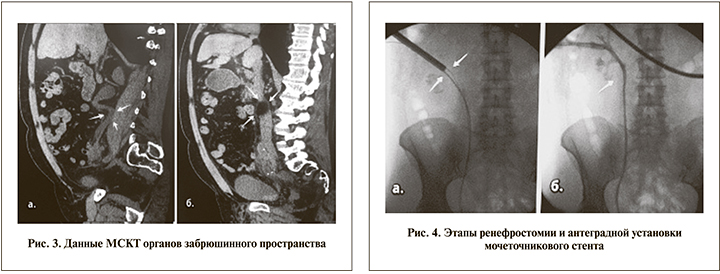

На 7-е сутки после КУЛТ отмечено отхождение нефростомического дренажа справа, что сопровождалось повышением температуры тела до 39оС. В тот же день выполнена МСКТ: выявлен инфильтрат вокруг мочеточника в средней его трети, вне просвета мочеточника определялись резидуальные осколки конкремента. Сам мочеточник на этом уровне достоверно не прослеживался. Визуализировалось геморрагическое содержимое в нижней трети мочеточника и в просвете мочевого пузыря. Правосторонний уретерогидронефроз до средней трети, камни левой почки (рис. 3).

Все вышесказанное послужило основанием для выполнения пациенту в экстренном порядке чрескожной пункционной ренефростомии и антеградной установки антирефлюсного стента (рис. 4).